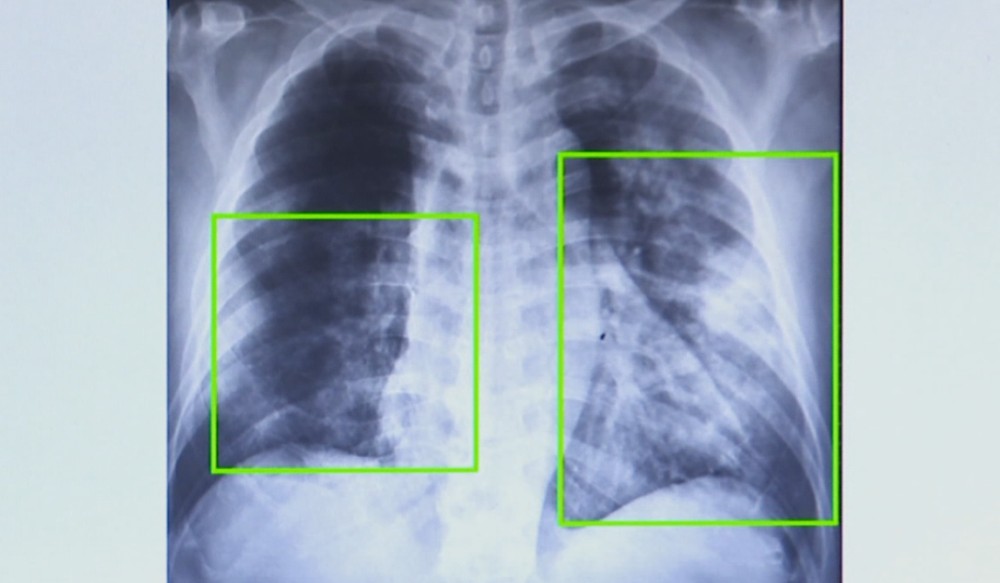

Casos de pneumonia disparam em SP e especialistas alertam: baixa vacinação impulsiona avanço da doença

Os casos de pneumonia têm crescido de maneira acelerada em todo o estado de São Paulo, pressionando a rede pública de saúde e acendendo um alerta entre profissionais da área. Apenas entre janeiro e agosto deste ano, a Secretaria Estadual da Saúde contabilizou 202.357 atendimentos por pneumonia, número que representa um aumento de 20% em comparação ao mesmo período do ano anterior, quando foram registrados 167.263 casos. O avanço ocorre em ritmo mais intenso em diversas regiões, como Campinas, onde o total de atendimentos chegou a dobrar, e Piracicaba, que também apresentou crescimento expressivo de 20%.